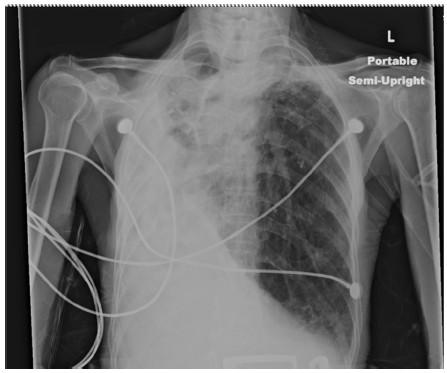

Postpneumonectomy syndrome is a rare condition that is characterized by dyspnea resulting from an extreme mediastinal shift and bronchial compression of the residual lung following surgical pneumonectomy. It is even rarer for this syndrome to present in patients without a history of prior lung surgery but induced by autopneumonectomy due to parenchymal disease, an entity termed 'postpneumonectomy-like syndrome'.

We present a rare case of a 91-year-old Puerto Rican man presenting with progressively worsening dyspnea with a history of pulmonary tuberculosis diagnosed 40 years earlier who developed severe unilateral lung fibrosis. Plain X-ray and computed tomography scans confirmed the presence of postpneumonectomy-like syndrome secondary to his parenchymal lung destruction. The patient developed cor pulmonale due to his extensive lung disease and as a consequence was not a suitable candidate for surgical intervention. The patient was otherwise stable until he developed acute respiratory distress from an acute upper gastrointestinal bleed and died four days into his hospital course.